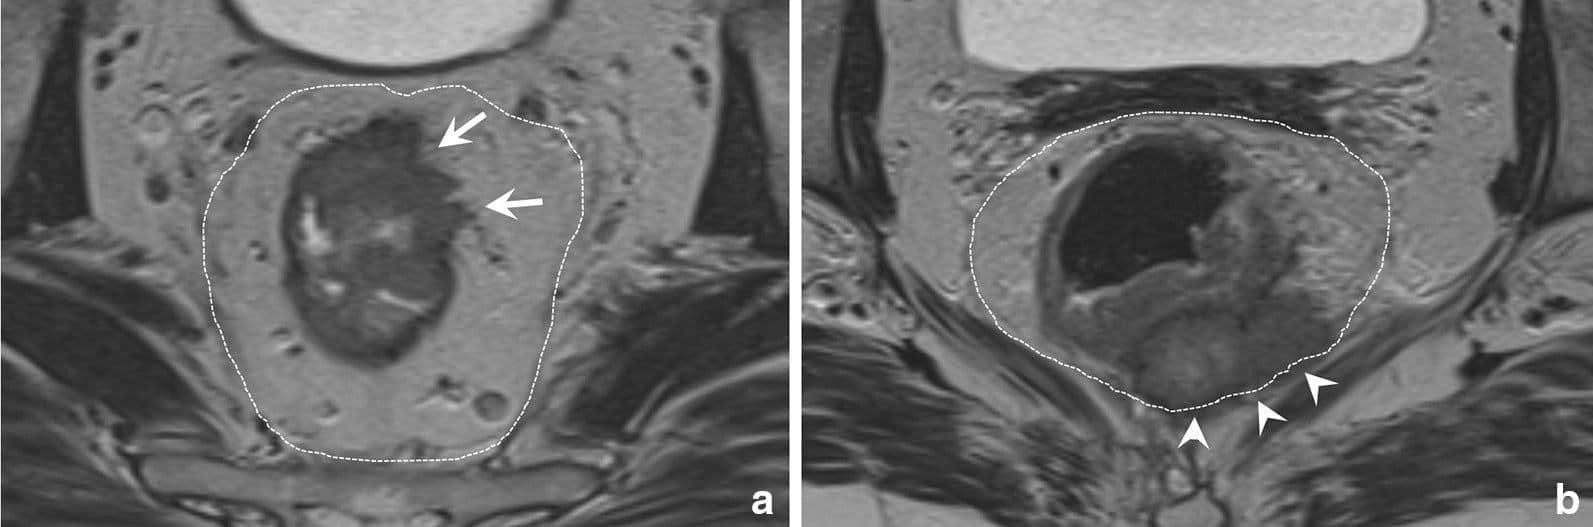

- Т4а або перитонеальна інвазія підозріла у випадку зміненої інтенсивності сигналу, потовщення або вузловатість очеревини, але не у випадку, коли пухлина прилягає до очеревини.

- Т4b включає залучення суміжних органів малого тазу, враховуючи матку, яєчники, піхву, сімʼяні міхурці, сечовий міхур, сечоводи, сечівник, кістки або наступні мʼзові структури: затульні, грушоподібні, ішиококцигеальні, пубококцигеальні мʼязи та леватори. Також консенсус пропонує додати в цю категорію залучення наступних структур: екстрамезоректальні судини, сідничні та крижові нерви, сакроспінозні та сакротуберозні звʼязки і мʼякі тканини за межами MRF – жирова клітковина затульного, клубового та ішиоректального просторів.

Важливо відмітити, що залучення мезоректальної фасції (MRF), перехідної складки очеревини (PR), залучення внутрішнього анального сфінктера або інтерсфінктерного простору – не є Т4b.